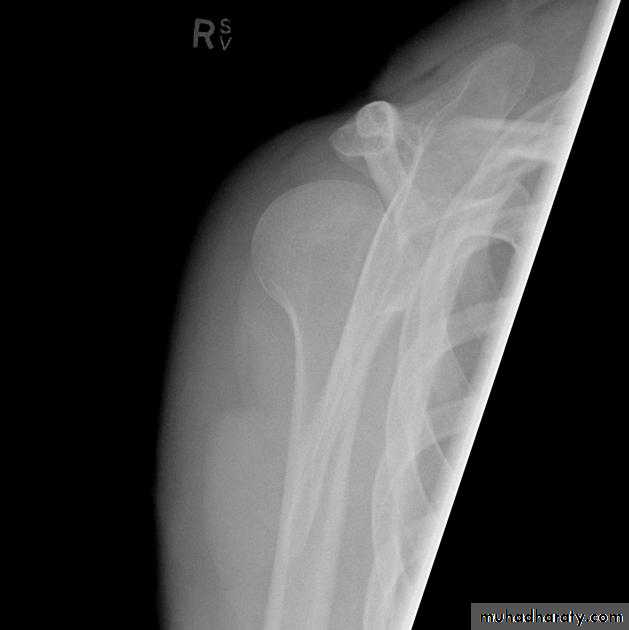

Posterior shoulder dislocation:

* very rare & form about 2-4% of shoulder dislocation.

* Posterior dislocation may be missed initially on frontal radiographs in 50% of cases, as the humeral head appears to be almost normally aligned with the glenoid.

*the internally rotated humeral head takes on a rounded appearance known as the light bulb sign.

*may be associated with posterior glenoid rim or lesser tuberosity.